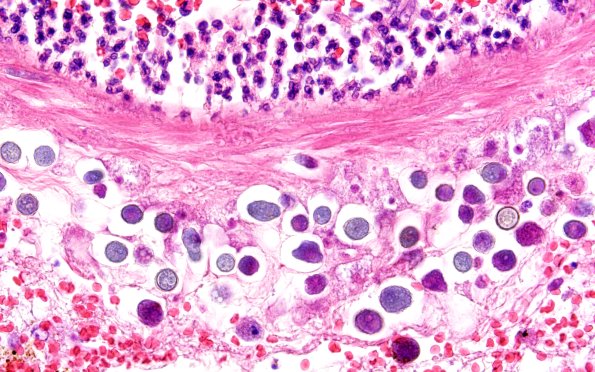

Washington University Experience | INFECTION | Protozoa | Ameba | 10A13 Acanthamoeba (Case10) 60X

10A13-15 Higher magnification images show the organism in a trophozoite form and as cysts (arrows, 10A15). It is thought that formation of cysts in tissue differentiates Naegleria fowleri from Acanthamoeba sp. The clinical diagnosis in this patient was Acanthamoeba but it is unclear if more sophisticated molecular analysis was performed. (H&E)